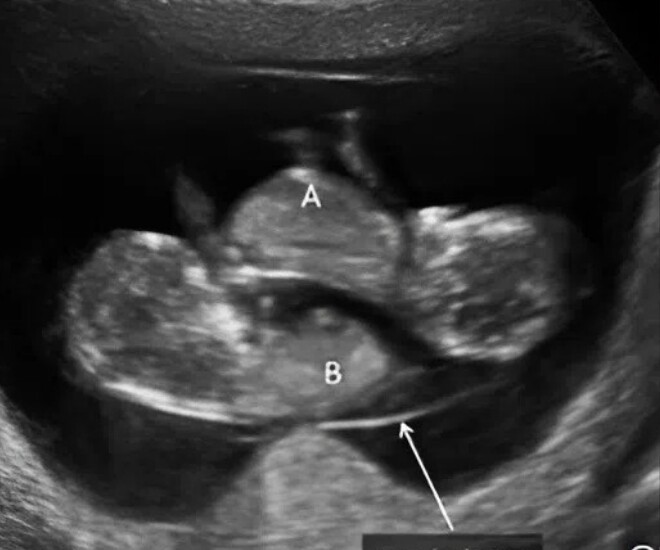

Hoá ra cô đang mang thai đôi 1 bánh nhau, 2 buồng ối - Ảnh minh hoạ.

Tuy nhiên, bác sĩ lại chặn đứng niềm vui đó, nói cô: "Đừng mừng vội", bởi đây không phải song thai thông thường mà là song thai một bánh nhau và hai buồng ối, thuộc nhóm thai kỳ nguy cơ cao.

Theo bác sĩ, với song thai thông thường, mỗi thai nhi có một bánh nhau riêng biệt nên phát triển tương đối độc lập. Nhưng trong trường hợp này, hai em bé dùng chung một bánh nhau, hệ thống mạch máu có thể liên thông, dễ dẫn đến tình trạng phân bố máu không đều. Một thai có thể nhận quá nhiều máu trong khi thai còn lại thiếu hụt, gây nguy hiểm cho cả hai.